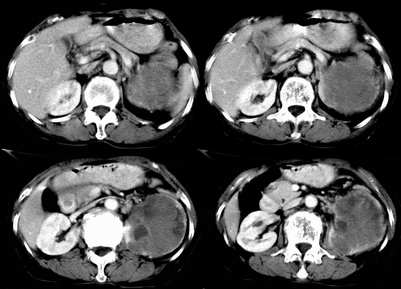

病患,女,69岁,左侧腰部不适,偶感疼痛2个月余,无化验室检查,行彩超发现左侧肾区实质性肿物,后行ct检查,结果同上。

左肾不规则软组织肿块,内见低密度坏死区,与正常肾实质分界不清,左肾明显增大,增强呈不规则条索状强化,肾盂及左输尿管上段扩张。肾周脂肪层受侵、模糊。印象:典型左肾癌。

平扫,表现为肾实质肿块,呈分叶状,肿块密度不均,内有不规则低密度区(陈旧性出血?坏死?)有的似呈囊性,增强明显不均一强化,与肾实质相比呈相对低密度的不均一肿块,肾周脂肪间隙可见,肾前筋膜未见增后,肾血管及腹主动脉旁未见肿大淋巴结影

三期抓的不错,典型的肾癌,且已累及肾盂及左输尿管上段